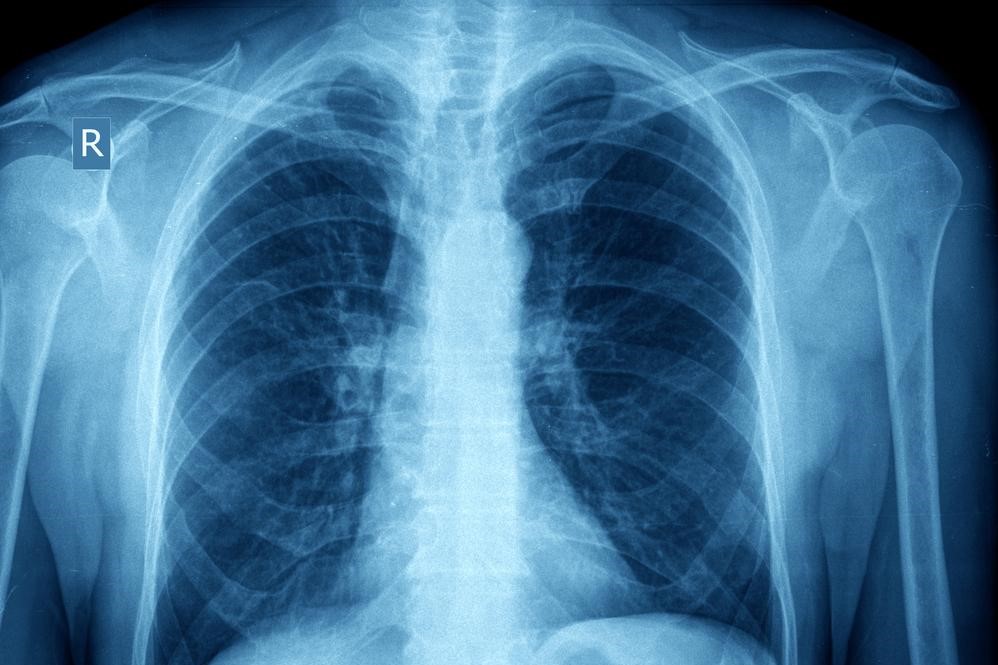

Pathology-and-pathophysiology-of-asthma